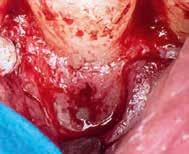

gyökércsatornában lévő pulpát is részlegesen eltávolítottuk. A sebészi feltáráshoz szükséges metszést a frenulum mellől indítottuk, majd intrasulcularisan, papillakímélő módon a szemfogig vezettük. A lebeny felemelését követően a csontos falú üregből a granulációs szövetet egy éles exkavátor segítségével eltávolítottuk.

A gyökércsatorna feltágítását és tisztítását hagyományos kemomechanikai protokoll szerint végeztük. Először passzívan levezetett kézi tűk segítségével a gyökércsatornát teljes munkahosszon szondáztuk, ezt követően gépi tágítókkal feltágítottuk, ezalatt nátrium-hipoklorittal öblítettünk, amelyet manuális agitációval aktiváltunk. A gyökércsatorna méretre történő tágítását követően, a következő átöblítőszereket alkalmaztuk: 3 percen keresztül ultrahanggal aktiváltunk 5,25%-os NaOCl oldatot, amelyet közben többször frissítettünk a csatornában, majd váltott átöblítés (17%os EDTA, 5,25%-os NaOCl) a smear layer eltávolítása céljából. Végső átöblítésként 5 percen keresztül ismét 5,25%-os NaOCl oldatot alkalmaztunk, amelyet ultrahanggal aktiváltunk és folyamatosan cseréltünk. A kemomechanikai megmunkálás és az átöblítőszerek alkalmazása során az elszívást a reszorbciós üreg széléhez helyeztük annak érdekében, hogy a kifolyó kémiai hatású szerek ne tudják a környező csont állományt roncsolni.

A gyökértömés elkészítése során meleg vertikális kompakciós technikát alkalmaztunk, sealerként pedig CeraSeal-t (Meta Biomed; 3. ábra) használtunk. A reszorbciós üreget Biodentine-nel (Septodont; 4. a–b ábra) töltöttük fel. A reszorbcióval érintett területtől koronális irányba elhelyezkedő csatornaszakaszt pedig tisztán meleg guttaperchával kezeltük. Ezt követően a lebenyszéleket visszafektettük, és varratok behelyezésével eredeti pozíciójuknak megfelelően rögzítettük. A koronai részt kompozit tömőanyag segítségével állítottuk helyre. Kontrollvizsgálatra 5, illetve 30 hónappal később került sor (5. ábra). A csontos telődés jelei már 5 hónap után észlelhetők voltak (6. a–c ábra). A 30 hónappal később végzett kontroll során sem találtunk csontban lévő lézióra, törésre vagy egyéb pathológiás elváltozásra utaló jeleket (7. a–b ábra)